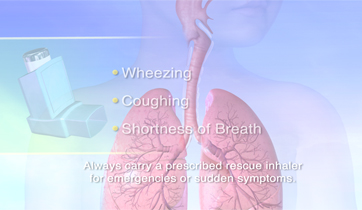

Asthma and its Triggers

Singulair, Merck

Rapp Collins Worldwide

New version in 2012 for UCSF

Patient education animation explaining Asthma and its triggers. The resulting constriction of the airways and the build up of mucus is explained, followed by tactics to maintain airflow and avoid attacks.